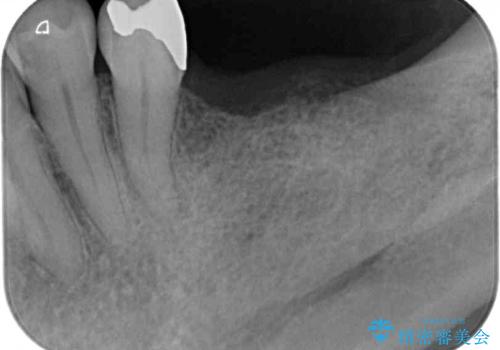

- 抜歯をしたものの、インプラントにするか入れ歯にするか悩んでいるうちに2年以上経過してしまったとのことで来院された患者様です。

自分の歯のように噛めるようにしたいとのことで、インプラントによる欠損補綴治療を行うこととしました。

インプラントにはストローマン社のSLActiveを使用し、埋入から補綴までおよそ3か月と、短期間で治療を進めることができました。